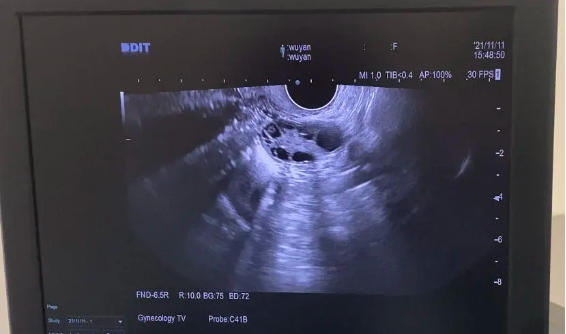

B超下卵巢